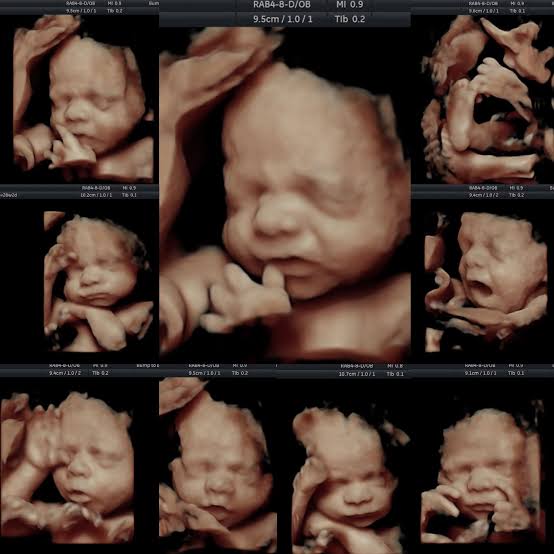

Growth Scan Ultrasound in Pregnancy

The Procedure: During the scan, a sonographer moves a handheld ultrasound probe across the abdomen to capture images of the baby. Measurements are taken of the baby's head circumference, abdominal circumference, and femur length to evaluate growth.